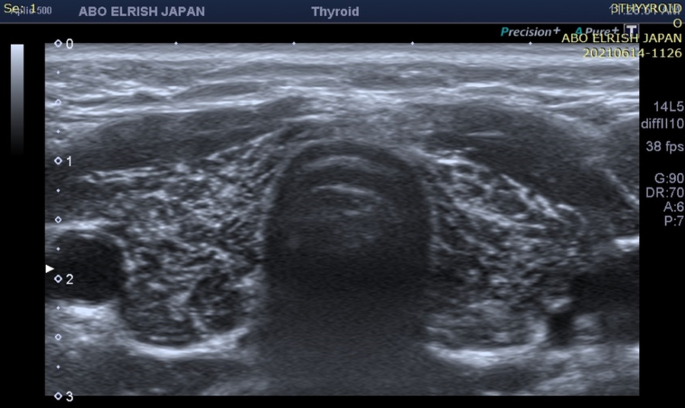

what thyroid pathology is shown here?

hemorrhagic thyroid cyst